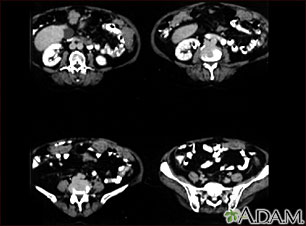

Peritoneal and ovarian cancer, CT scan

A CT scan series of the lower abdomen showing ovarian cancer that has metastasized (spread) to the peritoneum.